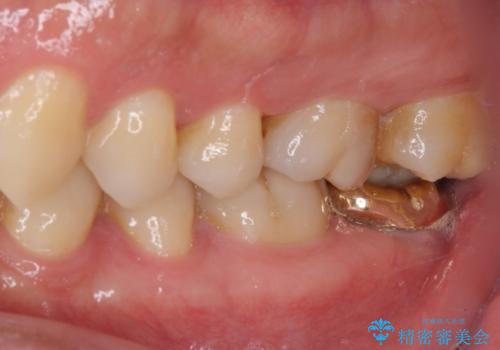

- 鼻づまりがひどく耳鼻科を受診したところ、虫歯が原因の可能性があるとのことで来院された患者様です。

レントゲン写真では根尖部に病変があるように見えたため、神経が失活しているのかチェックをしたところ、生活反応はありませんでした。

根管治療を行い、症状の経過を見て、セラミッククラウンにて補綴治療を行うこととしました。

根管治療後に耳鼻科症状は軽減したようですが、完全に良くなることはなかったため、副鼻腔の手術を受けたとのことでした。

レントゲン的には根管治療の治癒経過良好で、手術後に症状や違和感がなくなり、無事セラミッククラウンを装着することができました。